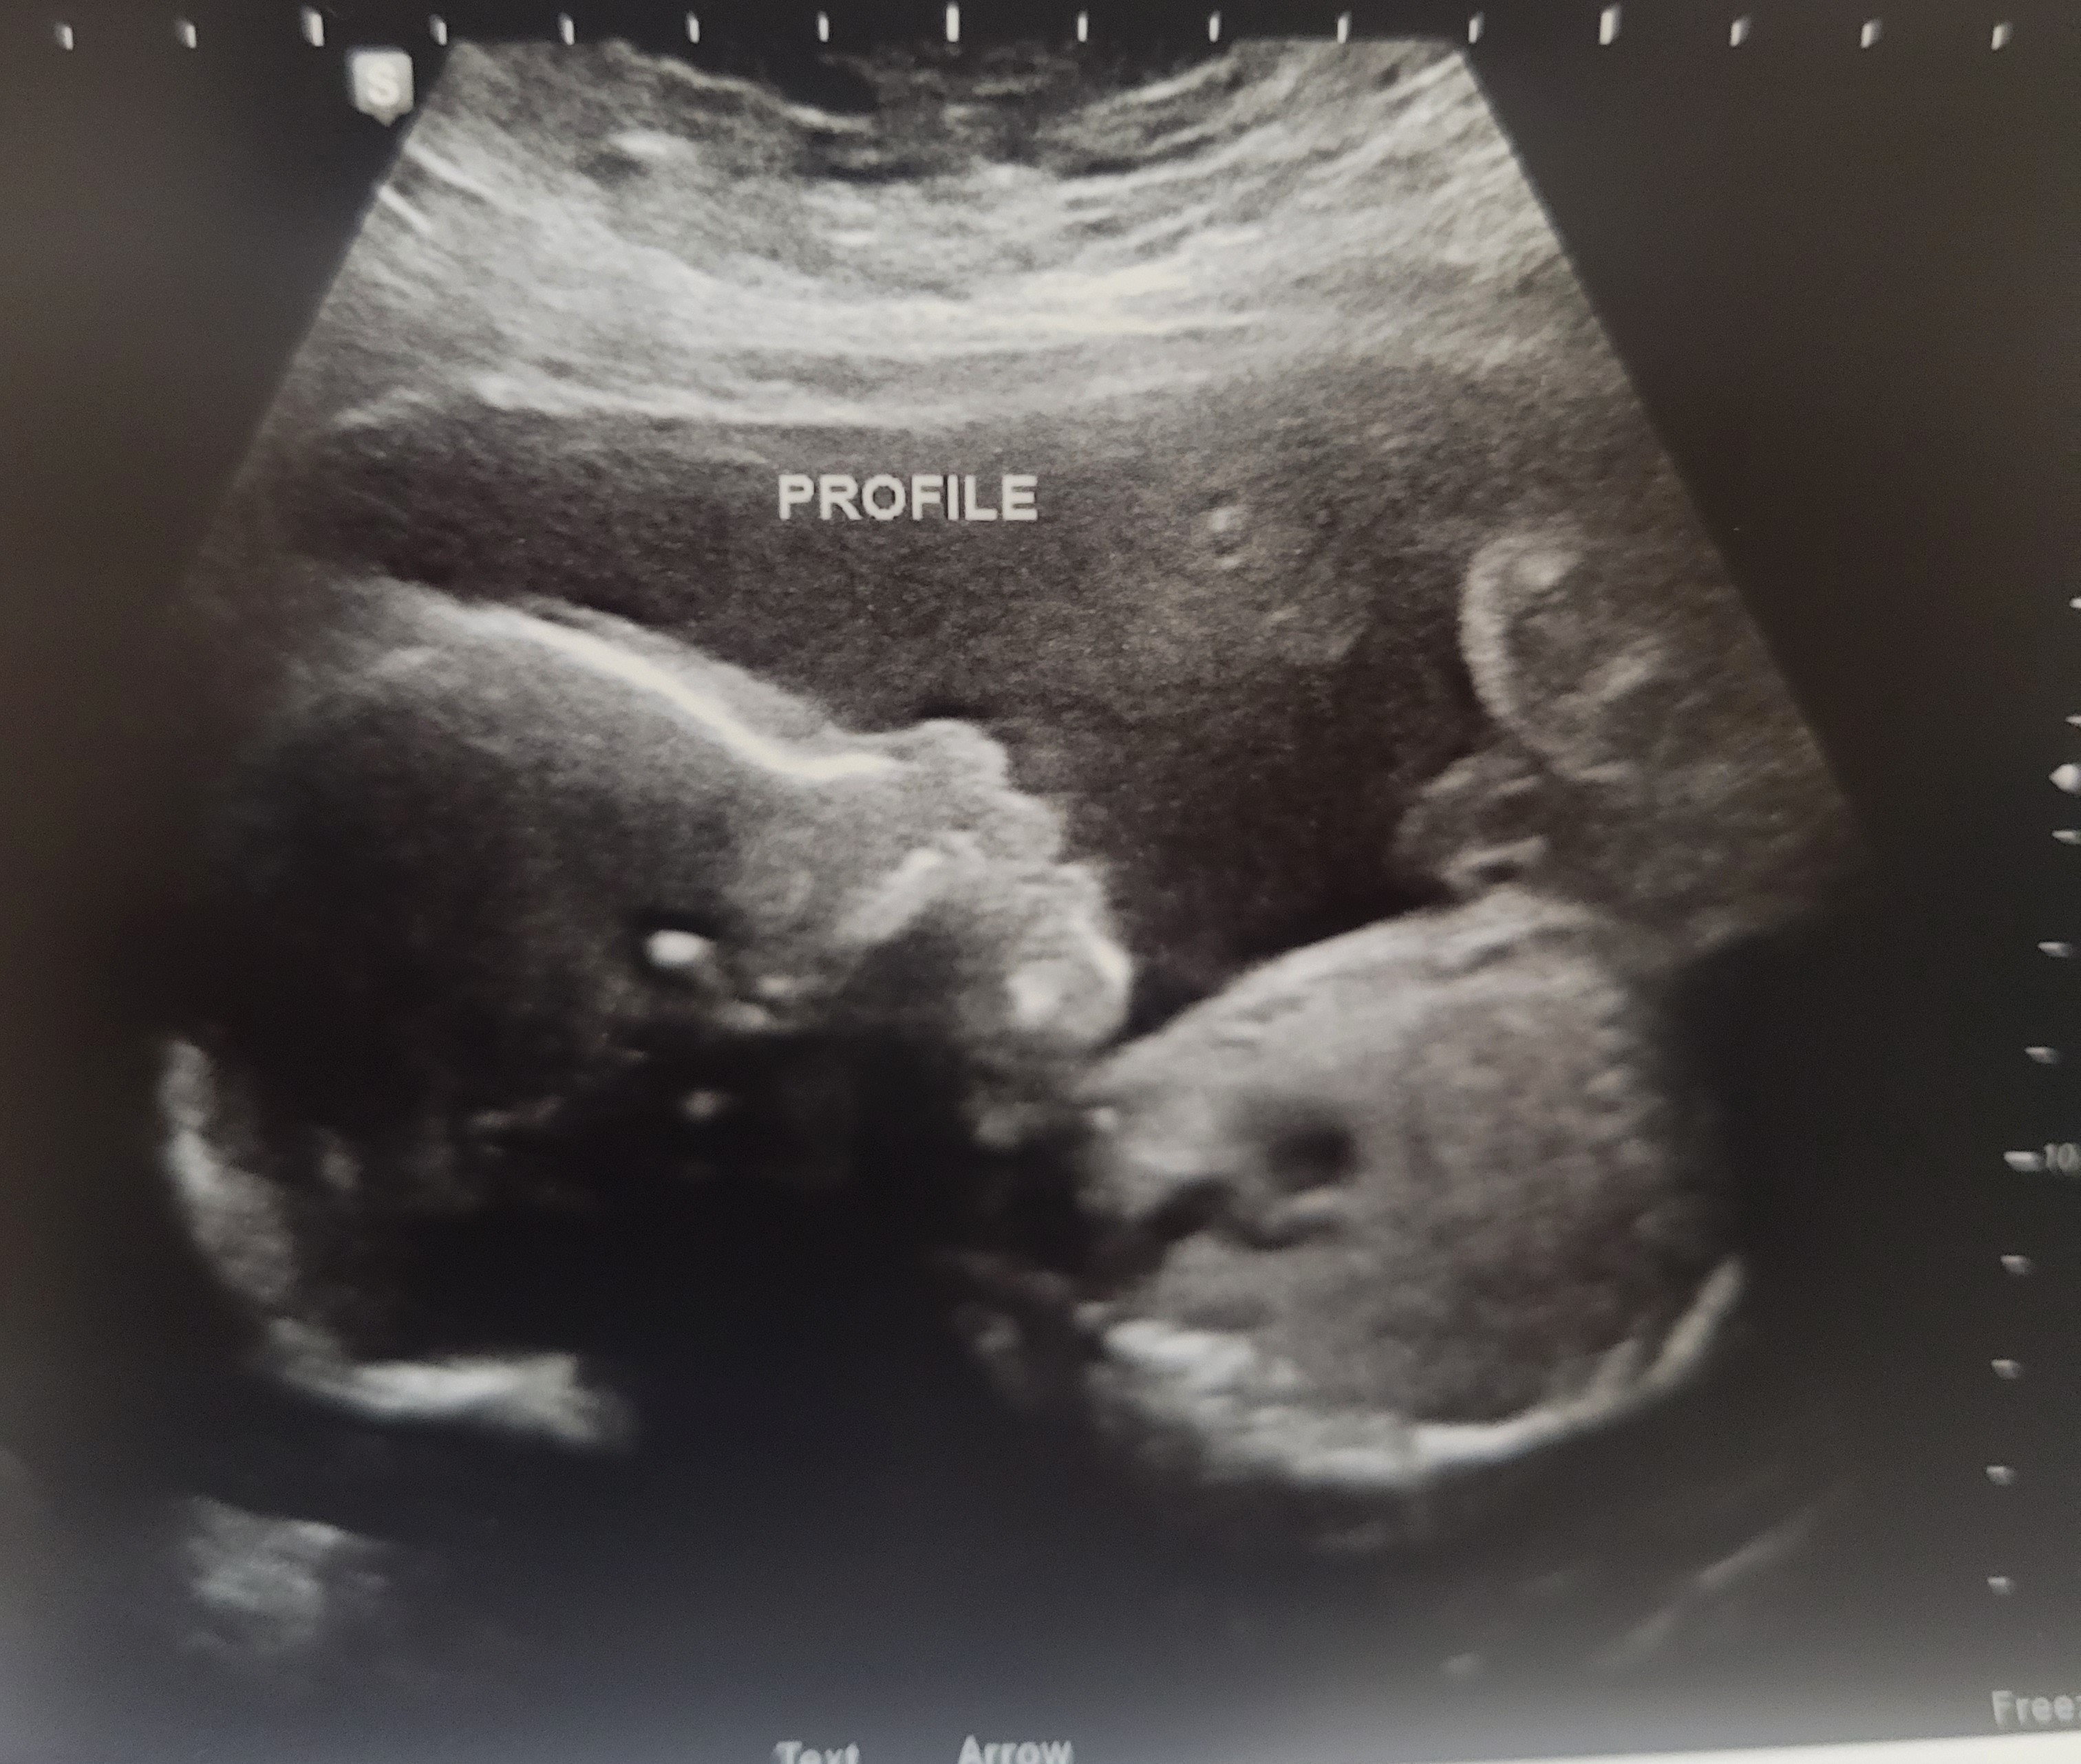

lindz42

member

June 2023

Report

4